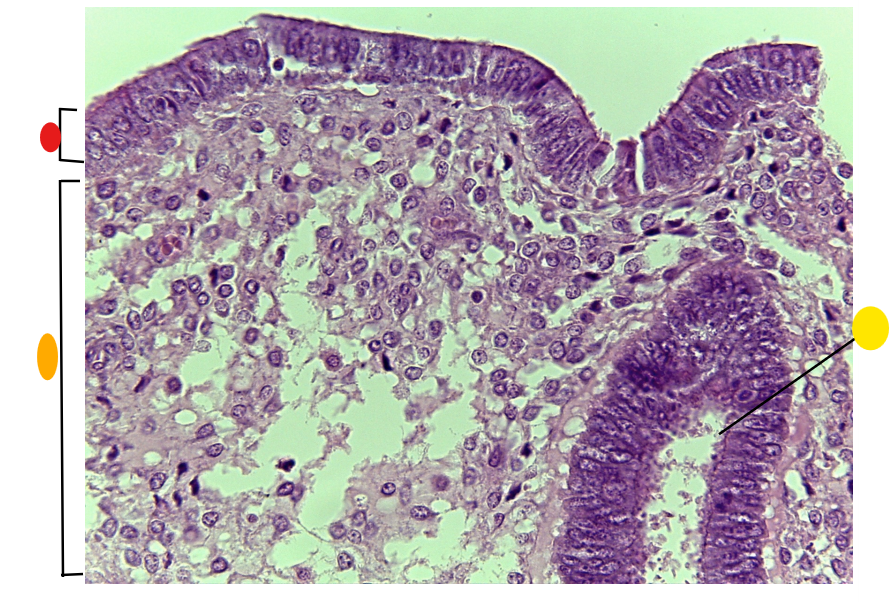

what is this

secondary follicle

what is this

tertiary follicle

red

tunica albuginea

orange

primordial follicles

red

primary follicle

orange

secondary follicles

what is this

tertiary follicle